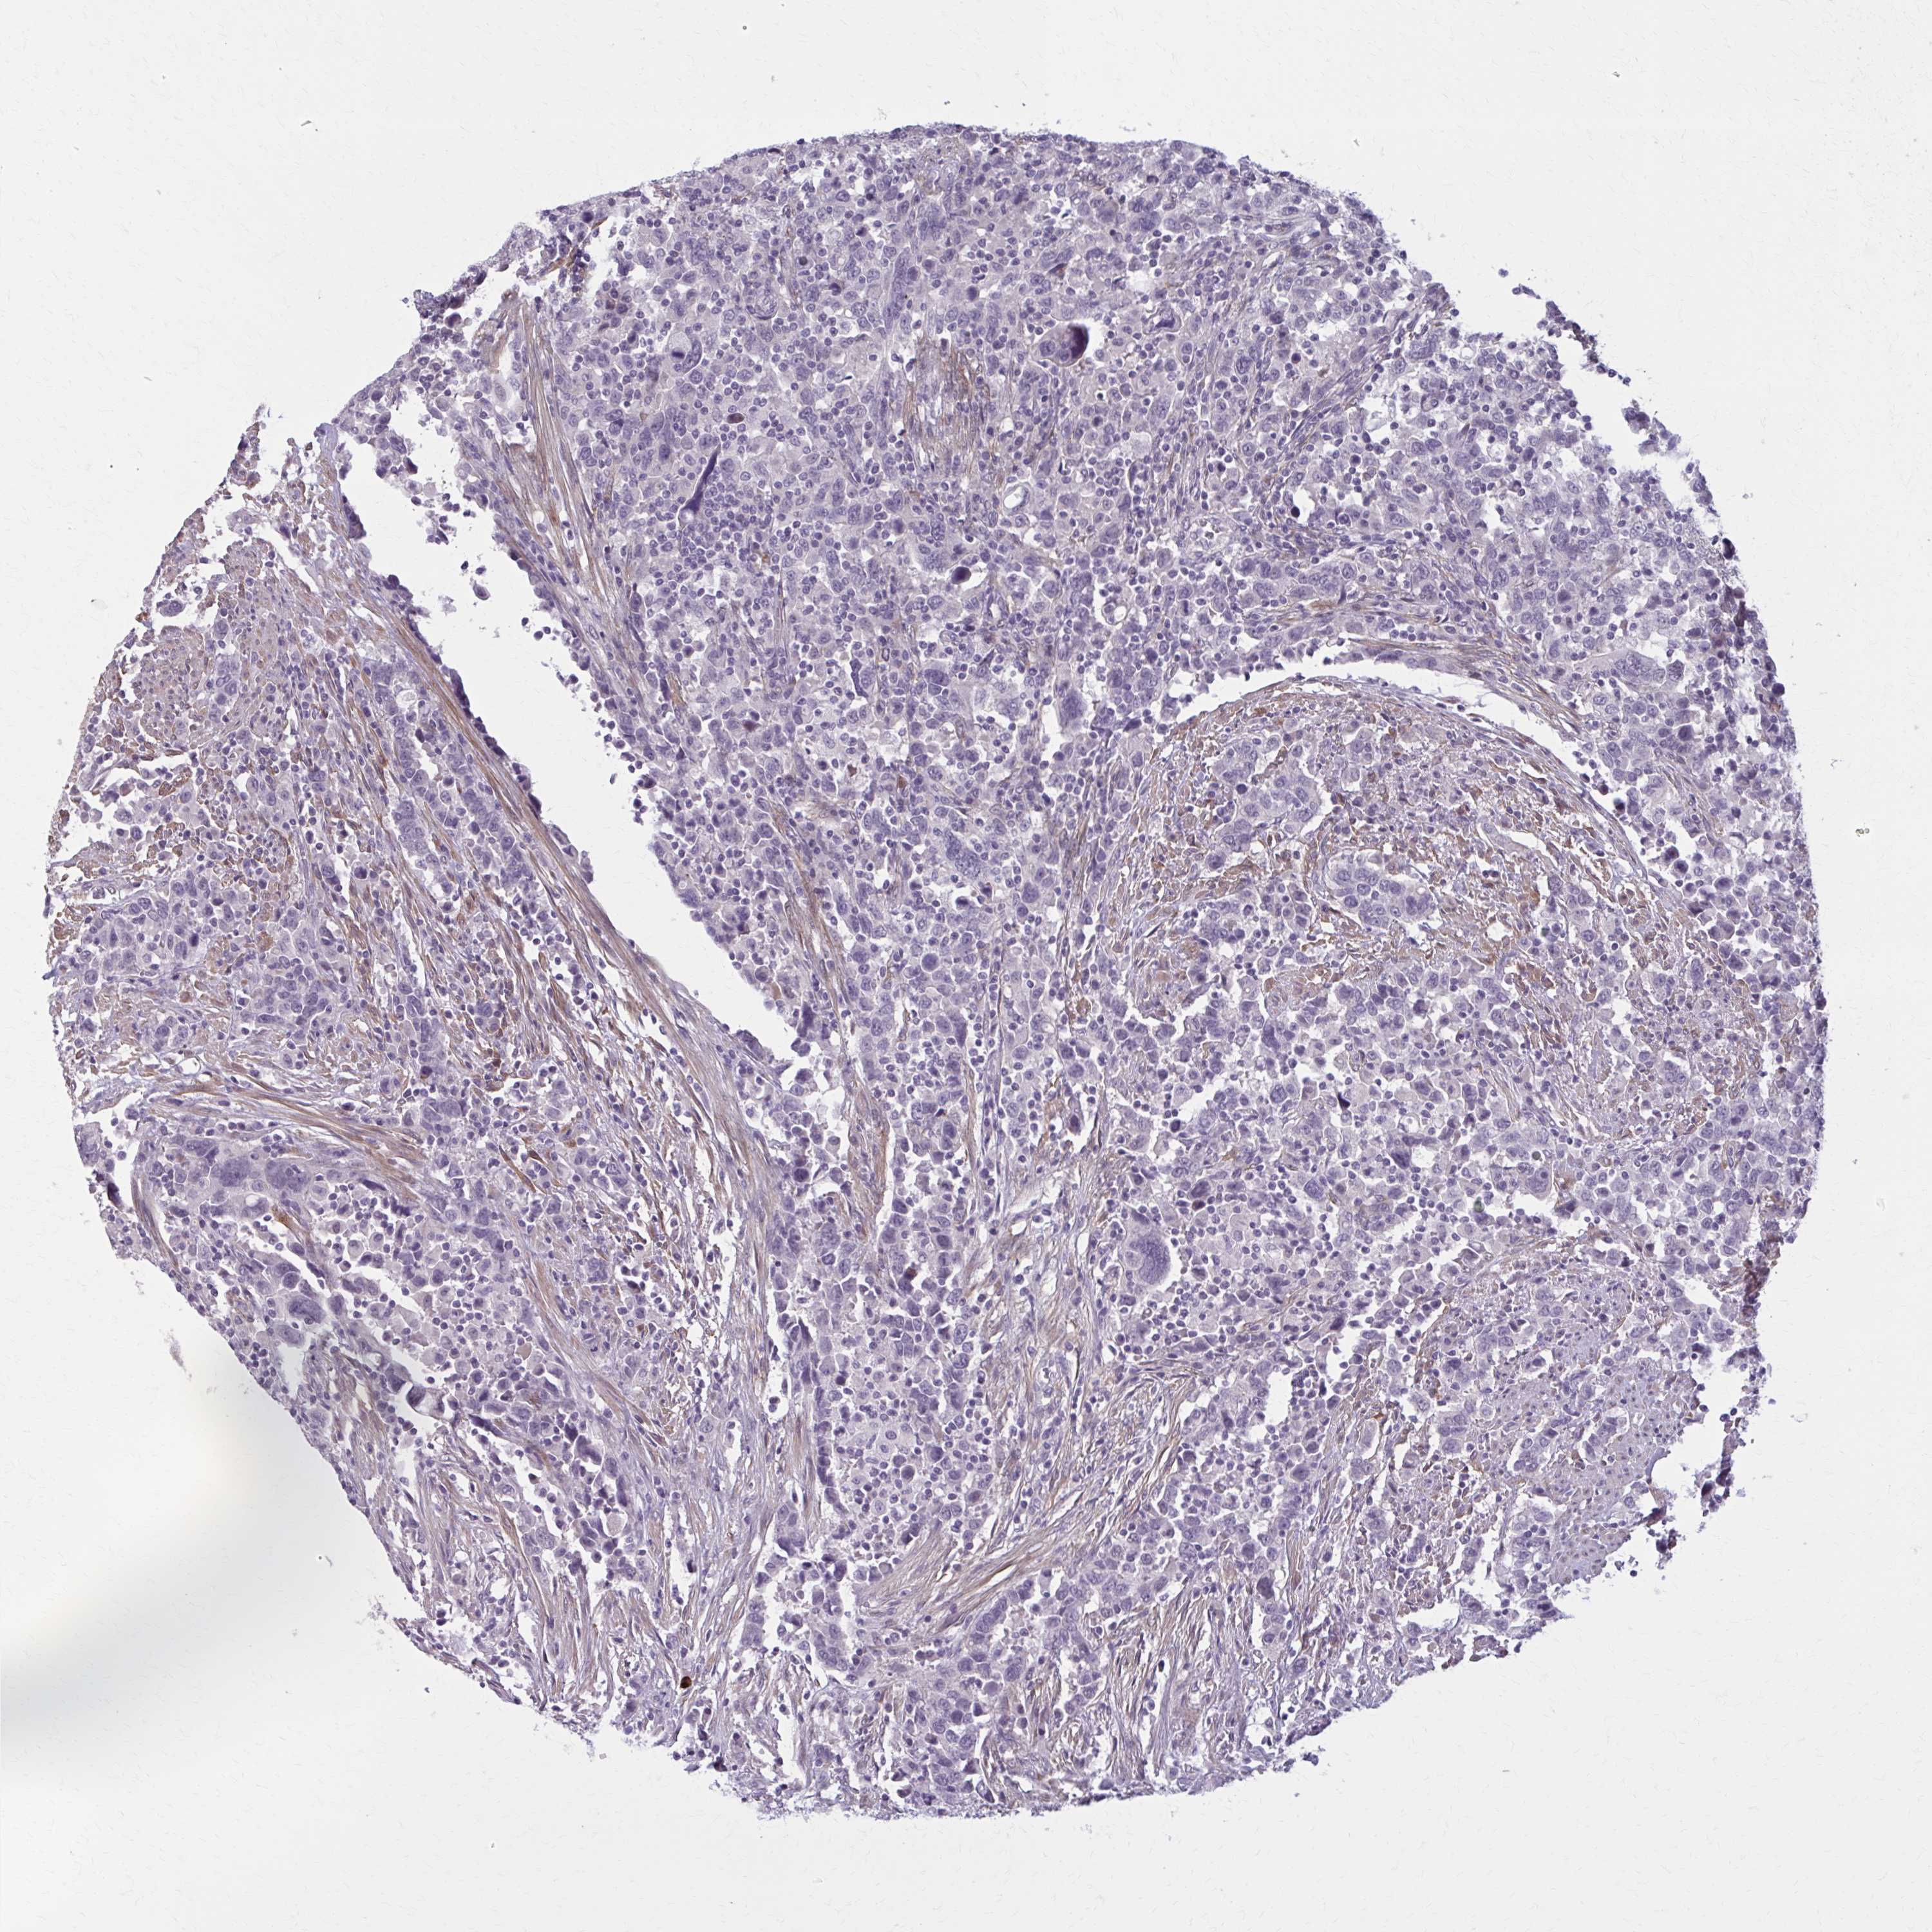

UROTHELIAL CANCER - Protein expressioni

A mouse-over function shows sample information and annotation data. Click on an image to view it in a full screen mode. Samples can be filtered based on level of antibody staining by selecting one or several of the following categories: high, medium, low and not detected. The assay and annotation is described here.

Note that samples used for immunohistochemistry by the Human Protein Atlas do not correspond to samples in the TCGA dataset.

Antibody stainingi

Antibody staining in the annotated cell types in the current human tissue is reported as not detected, low, medium, or high, based on conventional immunohistochemistry profiling in selected tissues. This score is based on the combination of the staining intensity and fraction of stained cells.

Each image is clickable and will lead to virtual microscopy that enables deeper exploration of all samples and also displays staining intensity scores, fraction scores and subcellular localization as well as patient and tissue information for each sample.

Antibody HPA058251

Antibody HPA058380

Urothelial carcinoma, Low grade

Urothelial carcinoma, High grade

Urothelial carcinoma, NOS